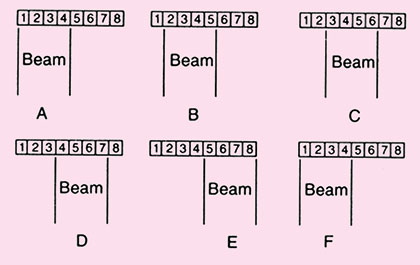

Linear Array

Transducer scan from this type of transducer are rectangular. The width of image and number of scan lines are constant at all depth.

An advantage of the linear array transducer is that it has good near field resolution. They are primarily used with high frequency (5–7 MHz) for evaluating soft tissues like scanning the breast, used in obstetrics and for thyroid gland (Fig. 1.16).

The disadvantage of these transducers is their large contact surface, leading to artifacts when applied to a curved body contour due to air gaps between the skin and transducer. Further more acoustic shadowing as caused by ribs can deteriorate the image. In general linear array transducer is not suitable for visualizing organs in the thyroid or upper abdomen.

Fig. 1.16: A linear sequenced array (side view). A voltage pulse is applied simultaneously to all elements in a small group: first to elements 1 through 4 (for example) as a group (A), then to elements 2 through 5 (B), and so on across the transducer assembly (C through E). The process is then repeated (F)